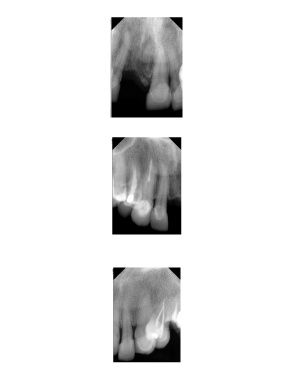

Page 23 - AAOMP Test

P. 23